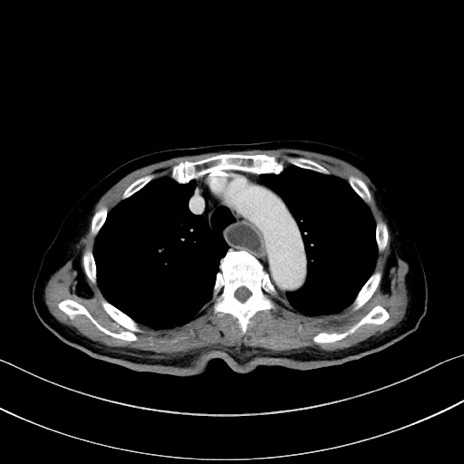

冠状断像

【症例】60歳代男性

【主訴】嘔吐

【現病歴】胃癌にて胃全摘後。食思不振が悪化し、夜中に嘔吐することがある。

【既往歴】胃癌、胃全摘、脾摘、胆摘後

【データ】WBC 5900、CRP 10.56